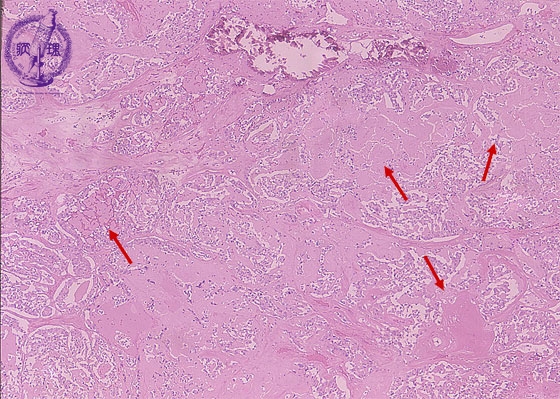

- (10)Medullary carcinoma of the thyroid

Microscopic findings (HE stain, low power view). The tumor cells are arranged in a solid or trabecular architecture. Deposition of amyloid (arrows) and calcification are visible in the tumor stroma.